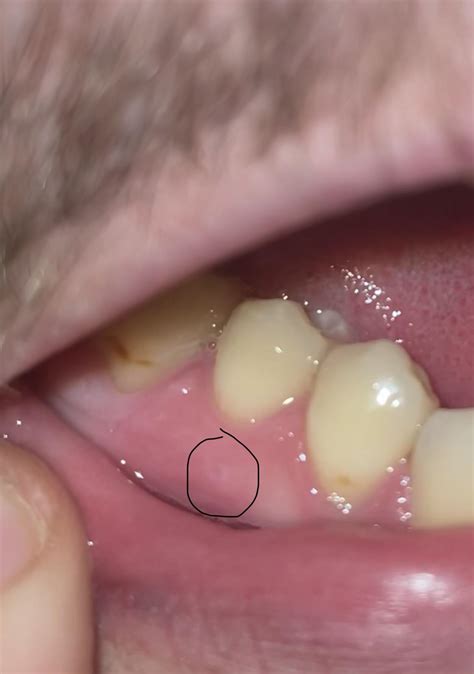

Dental Abscess

A dental abscess is a pocket of pus that forms due to a bacterial infection. It can develop at the root of a tooth or in the gums. While abscesses are often painful, some people may experience them as painless bumps on gums, especially if the infection is in its early stages.

Gum Disease

Gum disease, also known as periodontal disease, is an infection of the tissues that surround and support the teeth. In its early stages, gum disease may cause painless bumps on gums, along with other symptoms such as redness, swelling, and bleeding. If left untreated, gum disease can lead to tooth loss and other serious health problems.